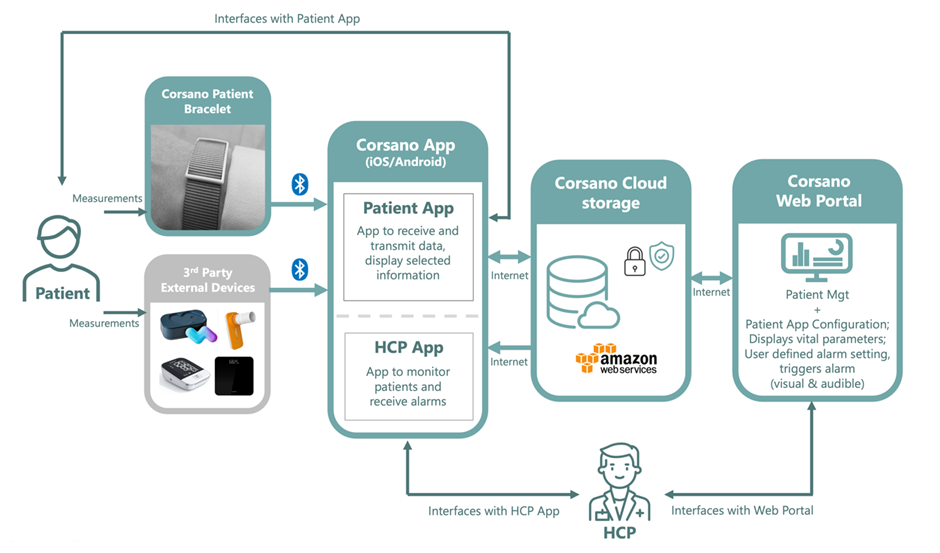

The AAN Digital Hub – reportedly designed to address gaps in diagnosis and treatment of the condition during the COVID-19 pandemic – focuses on facilitating virtual referrals for patients, as well as enabling knowledge exchange between primary physicians and specialists and their patients.

Unveiled at the 15th Annual Conference of the Saudi Association for Pulmonary Hypertension (SAPH), the AAN Digital Hub is a joint collaboration between Bayer and SAPH, the result of a “meeting of experts to discuss the future of PH treatment in the Kingdom.”

As well as offering virtual clinics and knowledge exchange, the platform will also reportedly serve as a detailed registry of PH patients in Saudi Arabia for medical professionals.

Patients will be able to access the hub – available on Android and iOS – during the app’s next release, scheduled to launch between April and May this year.